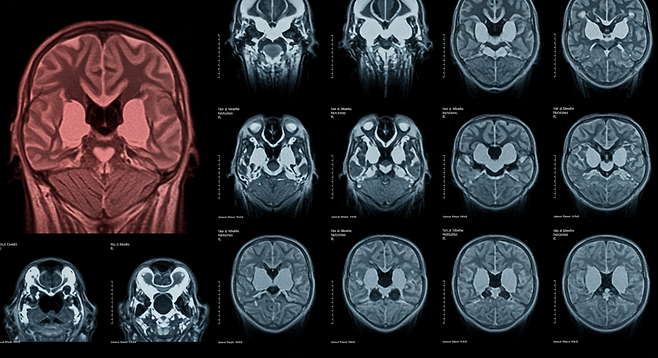

뇌경색, 왜 조기 발견이 중요할까?

뇌경색은 뇌혈관이 막혀 뇌조직이 손상되는 질환으로, 발생 후 3-4.5시간 이내에 치료받아야 후유증을 최소화할 수 있습니다. 하지만 많은 사람들이 초기 증상을 단순한 피로나 스트레스로 오해해 치료 시기를 놓치고 있습니다.